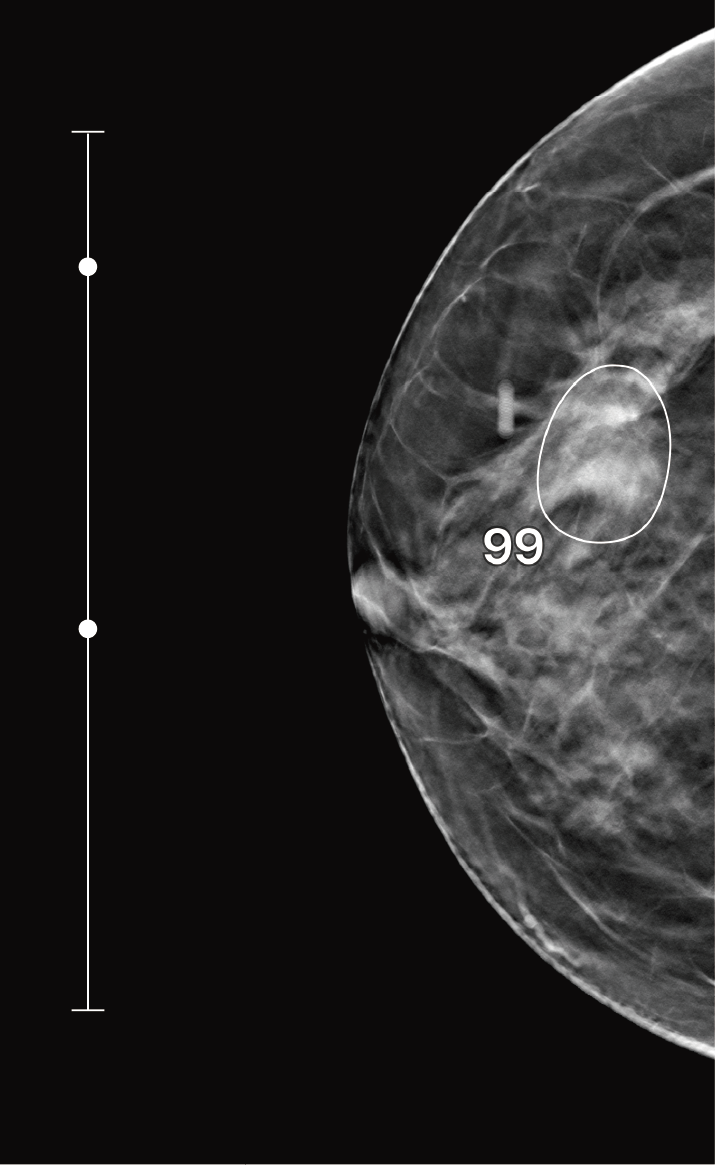

루닛 인사이트 DBT는 3D Tomosynthesis 영상을 분석하여 유방암 의심 부위를 검출합니다.

유방암 의심 부위의 존재 가능성을 0-100의 숫자로 나타냅니다. 숫자가 높을수록 악성 병변의 존재 가능성이 높습니다.

결과영상 화면에서 병변이 검출된 슬라이스의 번호와 점수를 확인(SC)할 수 있고, 클릭 시 해당 슬라이스로 바로 이동(CAD SR) 할 수 있습니다.